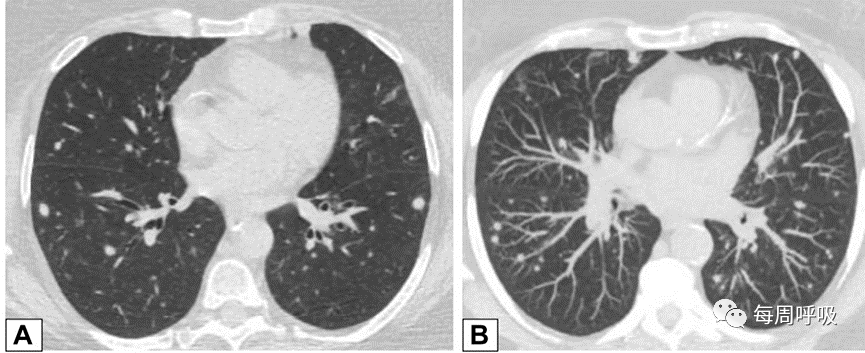

这种类型包括表现为线状不透明的实质条带,通常延伸到胸膜表面,通常先于磨玻璃样或实变(图15)。其他表现包括小叶周围增厚和具有反晕外观特征的病变(图16)。这个标志,也被称为“环礁征”,其特征是中央磨玻璃不透明(GGO)和外围实变。这些成像模式有着惊人相似的特征,通常可以在相同的情况下识别,甚至在同一张图像上。OP和慢性嗜酸性粒细胞性肺炎之间有相当多的共通之处,特别是当病变主要分布在上叶时。

图15条带活检证实为机化性肺炎的同一患者,间隔1年进行的轴位CT平扫(A)和增强(B)扫描显示,双肺下叶条带部分消退(A和B的箭头)。

图16 环礁征或反晕征。一名慢性持续性咳嗽和劳力性呼吸困难1年、体重减轻的32岁男性的CT扫描图像轴位(A)和冠状位(B)图像显示双侧中心磨玻璃样病灶完全被周围致密实变所包围,即反晕征或环礁征(A和B中红色箭头)。也存在不完全晕征(A和B中白色箭头)和小叶周围增厚(B中黄色箭头)。肺活检结果证实为机化性肺炎。